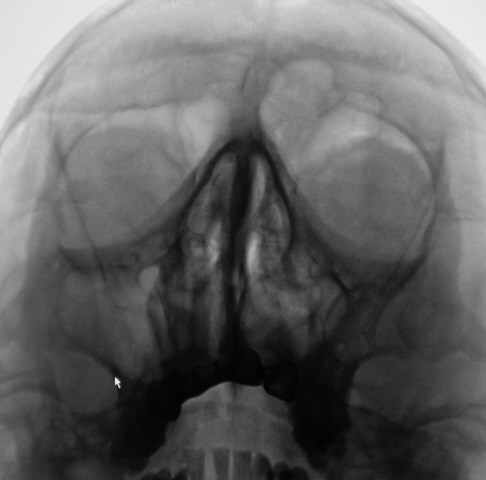

Ваше мнение коллеги по представленным снимкам и томограммам. Каждая иллюстрация представлена в двух вариантах - без обработки изображения и с "обработкой".

Четко не представляю. ) Случай интересный. Вероятно у него есть богатый анамнез с оперированной фиброзной дисплазией латеральной стенки пазухи? Какой не понять, снимки перевернуты.

Да. Перевернуты только томограммы, на которых левая сторона слева, а правая - справа. В анамнезе была операция, какая, пациент уточнить не может. В настоящее время  появились боли распирающего характера слева, чувство заложенности, направлен на исследование "без диагноза".

А перелома скуловой справа (напротив стрелки) не было?

Травм не было.